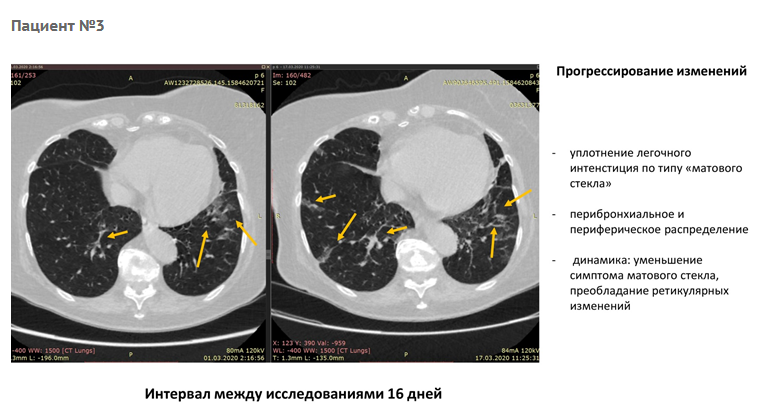

Через какое время делать повторное кт 113 фото